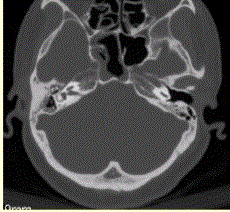

问题 患者男,20岁,外伤后右耳听力下降伴面瘫7d。临床检查,右耳传导性耳聋,发现脑脊液耳瘘。CT表现如下图。 颞骨骨折并发脑脊液耳瘘时应考虑合并

选项 A.鼓室盖断裂、鼓膜撕裂 B.鼓室盖断裂、鼓膜完整 C.前庭导水管断裂、鼓膜撕裂 D.前庭导水管断裂、鼓膜完整 E.咽鼓管断裂

答案 A